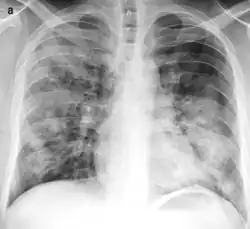

X-ray of bronchopneumonia: multifocal lung consolidation bilaterally.[3]

On gross pathology there are typically multiple foci of consolidation present in the basal lobes of the human lung, often bilateral. These lesions are 2–4 cm in diameter, grey-yellow, dry, often centered on a bronchiole, poorly delimited, and with the tendency to confluence, especially in children.